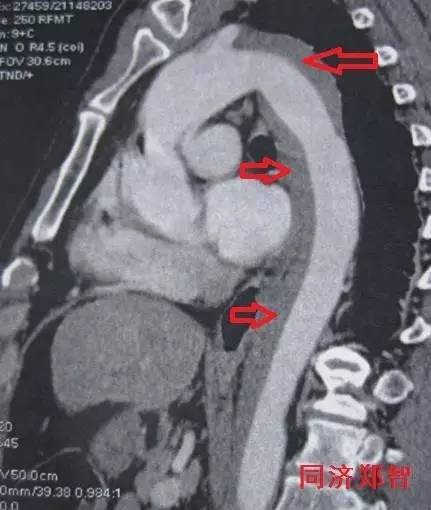

② Stanford A型 主动脉壁间血肿的CTA重建(图2),提示升主动脉和胸降主动脉的主动脉壁均有病变(红箭头所示)。

图2